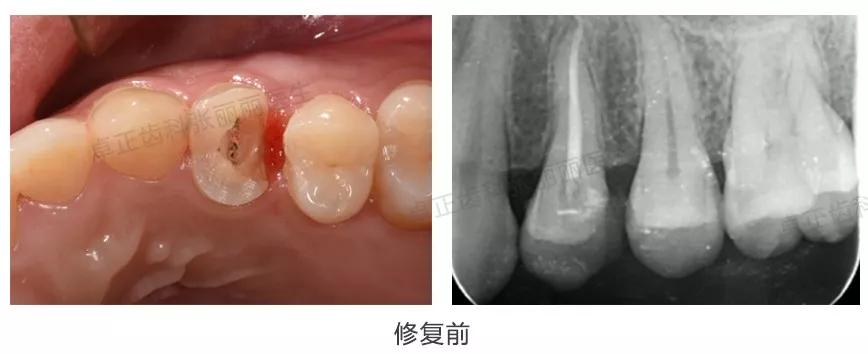

▍ 桩核冠修复

当牙体缺损非常严重,甚至累及牙根时,需要在根管内加桩来增加固位,再进行冠修复,称为桩核冠,这是在拔牙前能保存患牙的最后一种修复方式。目前临床上常用的桩核材料为纤维桩树脂核,金属桩核的使用逐渐减少。

临床案例:患者10年前上前牙烤瓷冠修复,因牙冠边缘不密合及牙龈反复红肿等问题,要求更换牙冠。拆除旧冠后,可见大量龋损,剩余牙体组织较少,不能为全冠提供固位,因此制作金合金桩核,为牙冠提供固位。